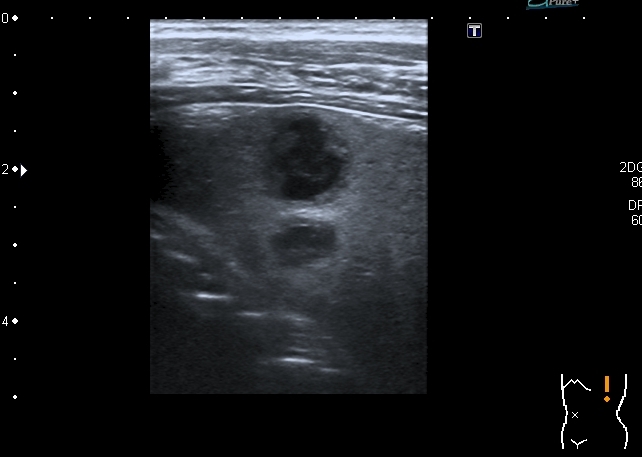

"Плохой"  подмышечный лимфатический узел, но справа. "Bad" axillar LN is seen

Hypoechoic lesions in the spleen. В селезёнке - множественные гипоэхогенные образования

The irregularity of the rib shown sonographically suggests an osseous process like Ewing sarcoma. However, I have seen three patients with similar findings with destruction of the sternum and adjacent ribs mimicking a tumour of the bone but caused by an infiltration of a Hodgkin’s lymphoma. A lymphoma would also be more consistent with the lesions found in the spleen. Regarding the morphology and shape of the mass in the axilla, I think this is a lymphnode.

In any case, I would recommend excluding a lymphoma in addition to Ewing sarcoma. Infiltration of the sternum or ribs caused by Mb. Hodgkin is an important differential diagnosis, which is also suggested by the splenic lesions in that case that are possible but not typical for Ewing sarcoma.